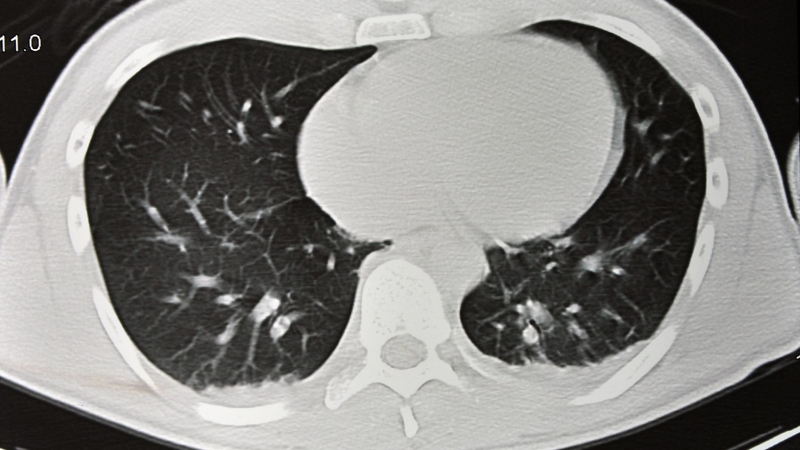

Chụp CT phổi là kỹ thuật sử dụng tia X kết hợp với hệ thống máy tính để tạo ra hình ảnh cắt lớp chi tiết của phổi và các cấu trúc lân cận. Khác với chụp X quang thông thường, hình ảnh CT cho phép quan sát phổi ở nhiều lát cắt khác nhau giúp phát hiện những tổn thương rất nhỏ mà X quang có thể bỏ sót.

Kỹ thuật này có thể thực hiện dưới dạng CT phổi thường hoặc CT phổi có tiêm thuốc cản quang tùy mục đích chẩn đoán. Nhờ độ phân giải cao, CT phổi giúp đánh giá chính xác nhu mô phổi, phế quản, mạch máu và hạch trung thất.